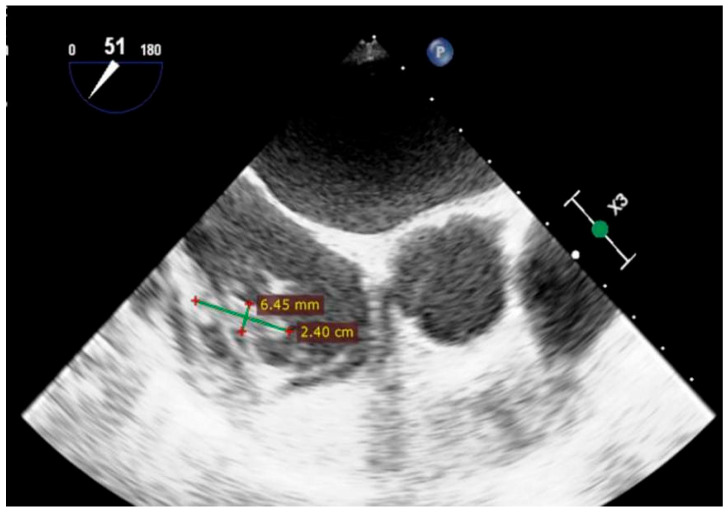

Background and Clinical Significance: Infective endocarditis (IE) is a serious condition with rising incidence, frequently caused by Staphylococcus aureus. However, cases involving rare congenital anomalies such as Gerbode's defect are uncommon. Case Presentation: This report presents the first documented case of IE in a patient with a congenital Gerbode defect complicated by DRESS syndrome-a severe, drug-induced hypersensitivity reaction typically triggered by antibiotics like oxacillin. A 65-year-old woman developed infective endocarditis involving vegetations on the cardiac device lead, the tricuspid valve, and adjacent to a Gerbode defect. The diagnosis was confirmed by positive blood cultures and echocardiographic findings. She received treatment with oxacillin. Subsequently, she exhibited clinical features consistent with DRESS syndrome, including rash, eosinophilia, and multi-organ involvement. Rapid recognition and management, including corticosteroid therapy and antibiotic modification, led to clinical improvement. Conclusions: This case highlights the importance of vigilance for DRESS syndrome in prolonged antibiotic therapy for IE, especially in the context of rare congenital cardiac anomalies. In addition, guidelines are needed to optimize the diagnosis and treatment of this potentially lethal complication.